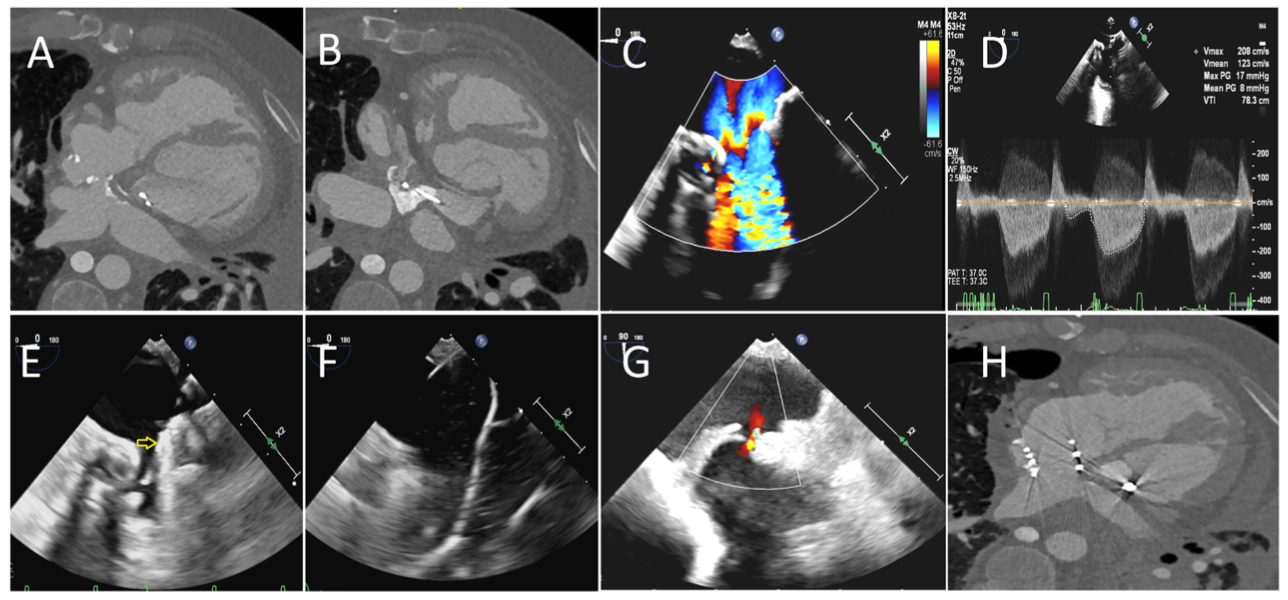

A 44-year-old man with history of D-transposition of the great arteries status post Mustard repair with pulmonary baffle obstruction was referred for further management. Cardiac computed tomography (CT) demonstrated calcific stenosis of the pulmonary venous baffle (PVB) outflow measuring 7.5 mm and systemic baffle stenosis measuring 7.4 mm (Figures 1A and 1B). Right heart catheterization demonstrated elevated superior vena cava (SVC) (15 mm Hg), mean pulmonary artery (54 mm Hg), and pulmonary capillary wedge (38 mm Hg) pressures. Angiogram of the SVC redemonstrated the SVC baffle stenosis and balloon angioplasty was performed with significant relief of stenosis.

A staged hybrid intervention of the PVB stenosis was performed (Video Series). Transesophageal echocardiogram (TEE) demonstrated PVB stenosis with a mean gradient of 8 mm Hg (Figures 1C and 1D). A right anterior mini-thoracotomy was performed to expose the right atrium. Under TEE guidance, right atrial puncture was performed and a 9-Fr sheath was inserted. Then a 0.35-mm Amplatz extra-stiff guidewire was advanced into the left pulmonary vein and the sheath was exchanged for a 16-Fr DrySeal sheath. Due to difficulty in obtaining an “en face” view on fluoroscopy, TEE was utilized to confirm appropriate stent position (Figure 1E). A 28-mm-long covered CP stent was mounted on a 16-mm Z-Med balloon (B. Braun Medical) and deployed under TEE guidance. The stent was sequentially postdilated with 18-mm and 22-mm noncompliant balloons under high pressure (Figure 1F). TEE demonstrated good expansion of the stent with residual mean gradient of 2 mm Hg. A 2-mm posterior left atrial wall perforation was noted on TEE, which led to small loculated hemopericardium limited to oblique sinus, which was confirmed on cardiac CT (Figures 1G and 1H). Repeat TEE showed thrombosed postprocedural effusion with no residual communication. The patient was discharged home with significant improvement in his exertional capacity. This case demonstrates the challenges and potential complications of hybrid PVB stenting in a patient with challenging anatomy.